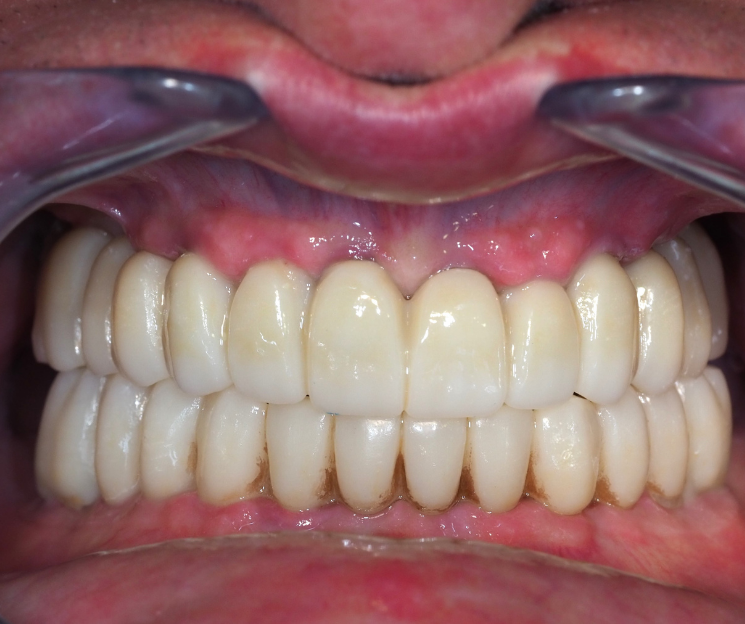

Clínica Dental especializada en la CDMX, Tijuana, Toluca, Cuernavaca, San Luis Potosí.  Colocamos  implantes dentales monofásicos de carga inmediata, también conocidos como implantes de una sola pieza. Somos una alternativa más rápida, estética y menos invasiva frente a los implantes tradicionales.

*Procedimiento: Colocación de implantes dentales monofásicos. A diferencia de los tradicionales (bifásicos), estos son de una sola pieza (tornillo y pilar integrados), lo que permite, colocar el implante y la prótesis provisional en una sola intervención o en un plazo de 3 días.

El tratamiento con implantes dentales está especialmente indicado para personas que han perdido una o más piezas dentales y desean recuperar su sonrisa a través de una solución fija, estable y definitiva, sin necesidad de prótesis removibles. Incluso aquellos pacientes que presentan poco hueso pueden ser candidatos, gracias a técnicas avanzadas que permiten trabajar con alternativas como la implantología monofásica. Además, es una excelente opción para quienes desean reemplazar prótesis removibles incómodas o poco estéticas, mejorando significativamente su calidad de vida, comodidad y confianza al sonreír.